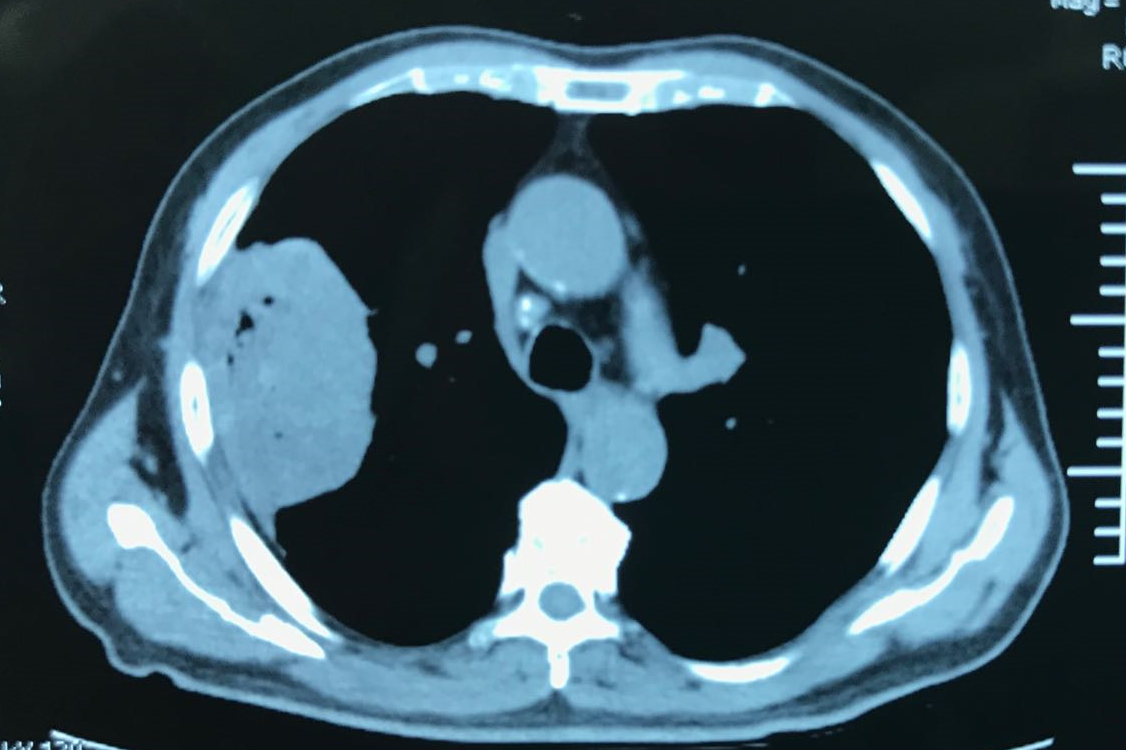

左胸壁巨大肿瘤

胸壁恶性肿瘤的影像学评估